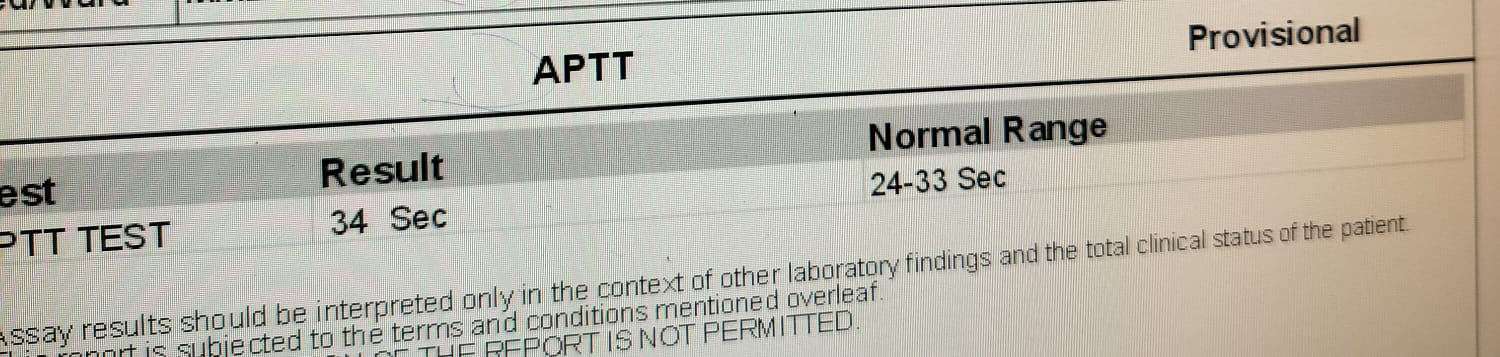

APTT 31

BLEEDING TIME :2 MIN CLOTTING TIME:4 MIN CRP:1.2 MG/DL

PT:15 SEC INR:1.11